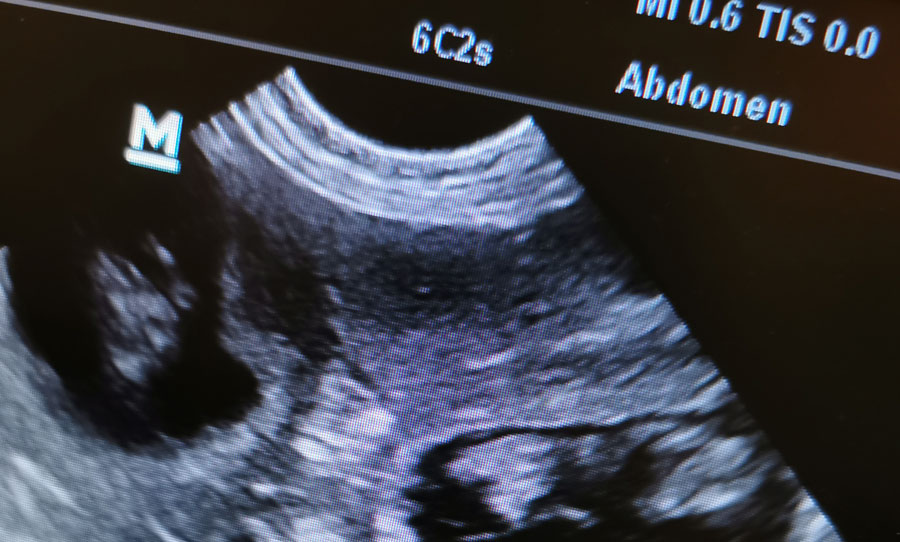

Ultraschalluntersuchung

Mittels der Ultraschalluntersuchung (Sonographie) ist uns eine gute, anschauliche Untersuchung vor allem der Bauchorgane möglich. Trächtigkeiten lassen sich sofort erkennen, aber auch Beprobungen und Punktionen, z.B. der Harnblase, Zystozenthese, sind leicht und sicher, meist sogar ohne Narkose durchzuführen.